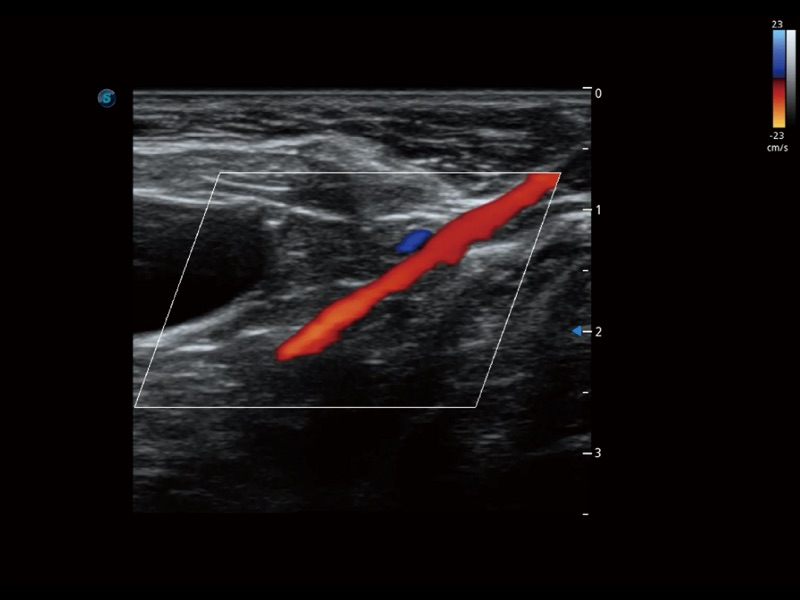

为精细结构及组织边缘提供高清晰度的图像和更大的成像视野。帮助减轻医生的用眼疲劳,快速精准获得测量的数据。

ProPet 70 全新的动物超声智能软件和丰富的探头群,为动物医生提供了高清晰度和精细分辨率的图像,无论在宠物、马科、畜牧还是实验室动物等应用中都可以轻松应对,为您的日常工作带来满意的体验。